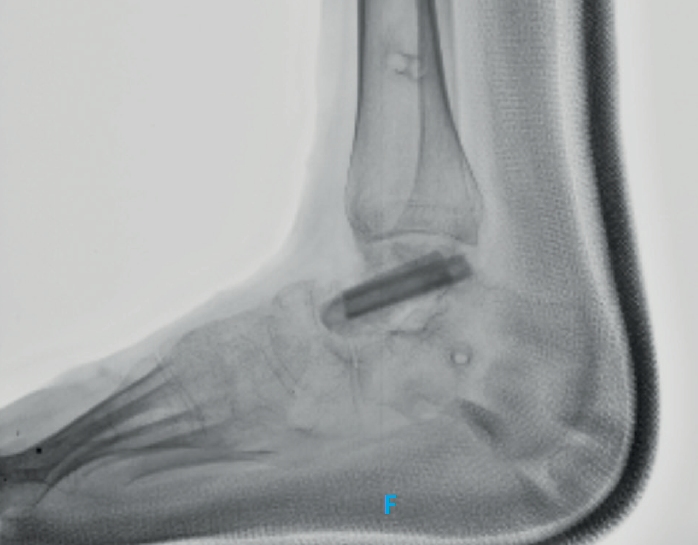

rpt.3602.fs2110029-figura8.png

Figura 8. Imagen de rayos X donde se evidencian signos de remodelación del injerto.

La paciente deja de utilizar la férula para iniciar la fisioterapia. Logra caminar sola sin ayuda y sin dolor, aunque persiste una leve limitación en los arcos de movimiento (Figura 9). En los rayos X a los 4 meses tras la operación se evidencia una mayor osificación del injerto (Figura 10).

rpt.3602.fs2110029-figura10.png

Figura 10. Radiografía a los 4 meses postoperatorios que evidencia una mayor osificación del injerto.